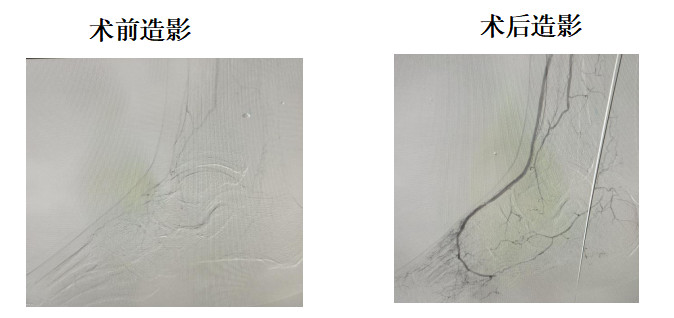

手术当天,糖足中心团队、麻醉科团队早早来到介入导管室,进行充分的术前准备。麻醉科尚冬青主任团队凭借丰富的麻醉手术经验,精准地为徐大爷实施了全身麻醉,确保手术过程中患者不会因疼痛或不适而躁动。随后,糖足中心副主任陈盛业、任澎医生在没有患者主观配合情况下,凭借精湛技术将导管送入患者下肢动脉,精准地定位到病变部位,对闭塞的动脉进行开通和扩张。整个手术过程紧张而有序,每一个环节都凝聚着医护人员的专注与努力。经过数小时的奋战,手术终于成功完成,闭塞的下肢动脉重新恢复了通畅,为徐大爷保住肢体带来了希望。术后,徐大爷各项生命体征平稳,患肢血运恢复良好。